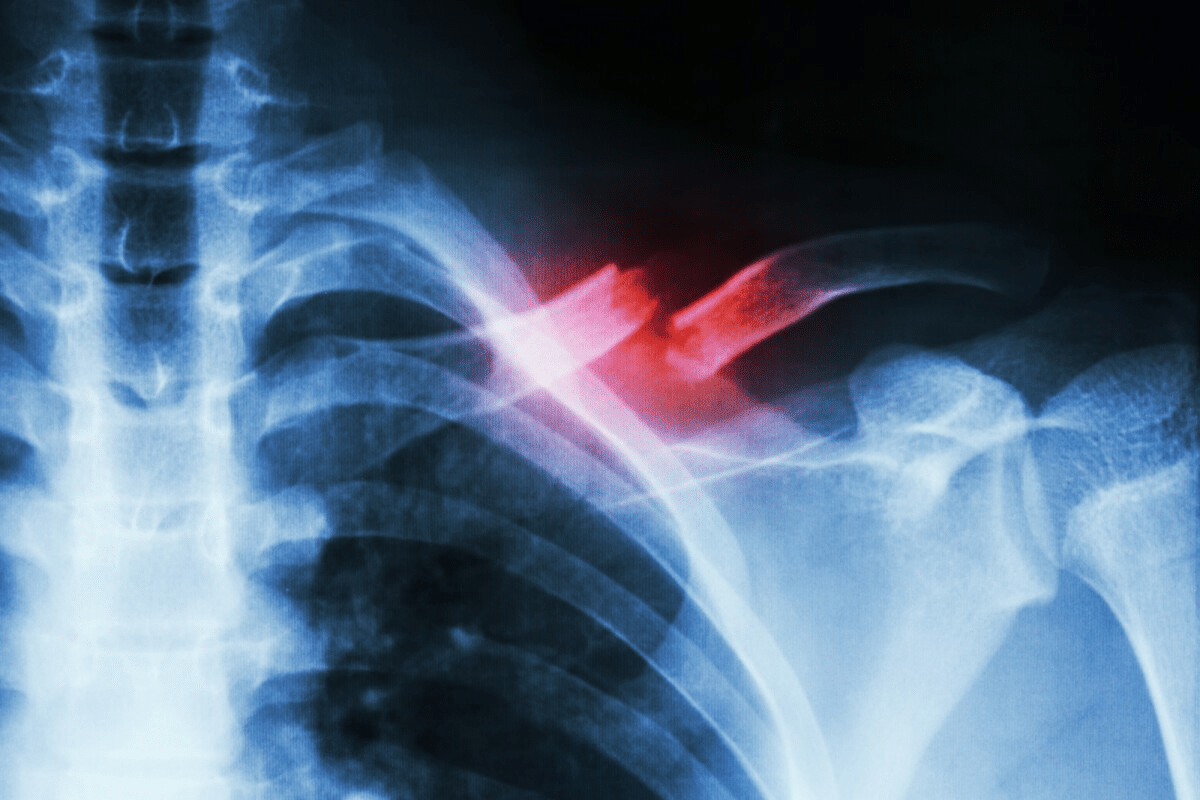

Types of Fractures: Classification and Characteristics

Understanding fractures is key in orthopedic medicine. It helps doctors decide the best treatment and predict how well a patient will recover. Fractures are sorted by how bad they are, where they happen, and what they look like. This information is vital for picking the right treatment.

Fracture Patterns and Their Significance

Fractures can be described by their pattern, like transverse, spiral, oblique, or comminuted. Knowing the fracture pattern helps doctors understand how bad the injury is and plan treatment. For example, a transverse fracture breaks straight across, while a spiral fracture twists around the bone, often from twisting injuries.

Identifying the fracture pattern is important for treatment and recovery. Different patterns might need different treatments, from casts and braces to surgery.

Diagnostic Imaging Techniques

Imaging tests help figure out if a bone is broken and how bad it is. X-rays are often the first choice because they show bone well. But, some breaks might not show up on X-rays.

CT scans or MRI are used when X-rays don’t work. CT scans help with complex breaks. MRI shows soft tissue injuries too.